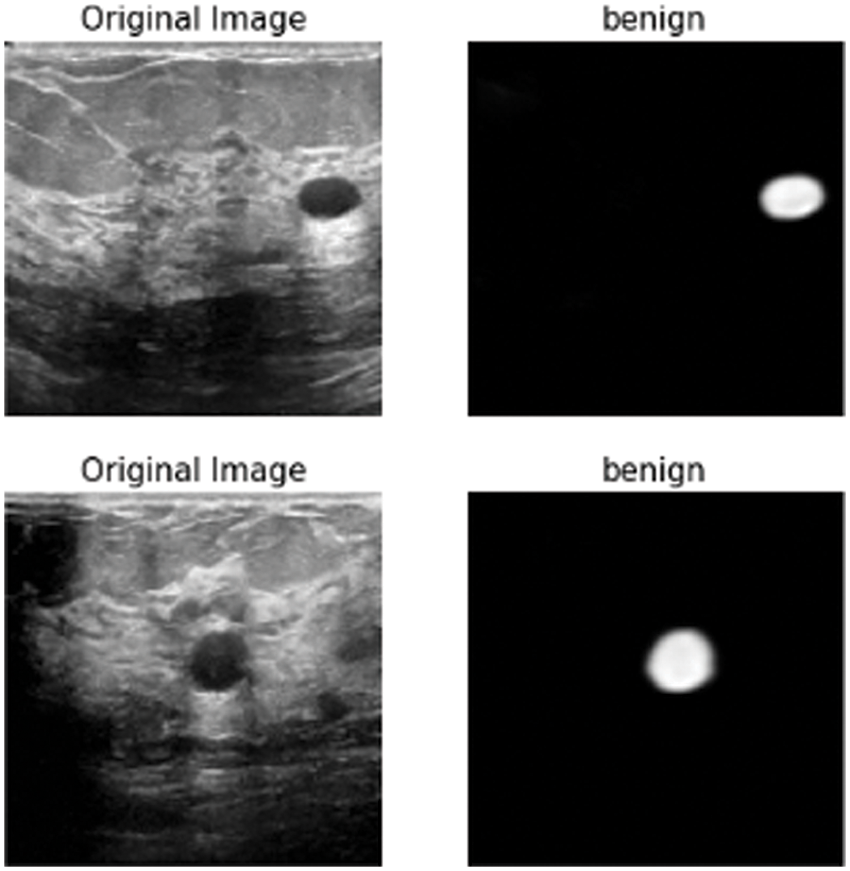

In this subsection, the framework shows the results after using U-Net architecture to segment the image after the process of denoising the image in the previous step. The U-Net model uses the result from the previous step after comparing the images of the five models and the level of noise. Tabs. 3 and 4 show the results after and before denoising the dataset of ultrasound, the results shows the enhancement of different metrics in the segmentation process after denoising the images, and the results also show the quality of u-net against the other methods, Fig. 10 shows the results of using U-Net in the segmentation process. The figure shows the ultrasound, mask, and predicted result using U-Net. Tabs. 5 and 6 show the results of classification of the segmented image into the malignant, tumor, and normal using different methods before and after removing noise, the results show the efficiency of methods after removing noise from images, and the results also show the efficiency of CNN against models. Fig. 11 shows the results of classifying the output into benign and malignant classes and Fig. 12 shows the results of removing noise in the enhancement stage.

Figure 11: Class of tumor results